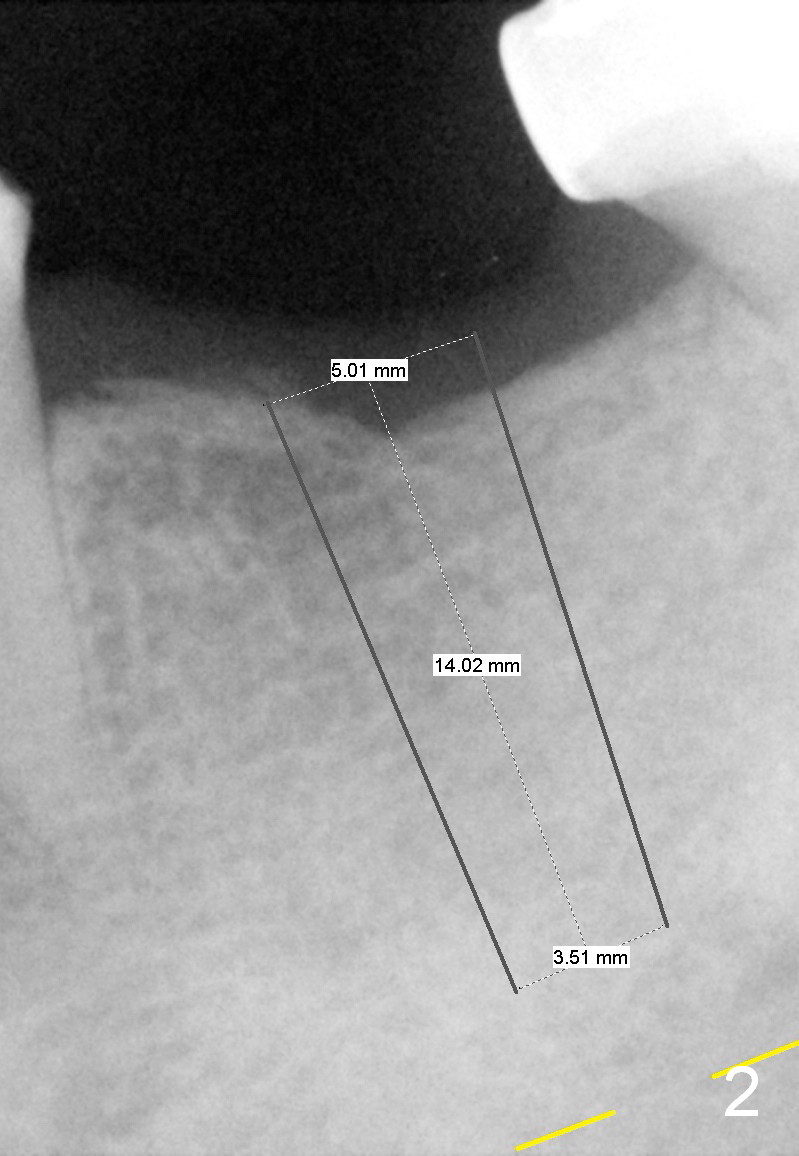

A 45-year-old man has lost the tooth #19 for about a decade (Fig.1).  In spite of this, the ridge is not particularly narrow.  The bone height is good for 14 mm bone-level implant (Fig.2).  After incision, initial osteotomy depth is 12 mm.  Insert a short parallel pin for occlusal check and a depth-marked parallel pin for X-ray.  When the depth is adjusted, use drills with stoppers to finish osteotomy.  If bone density is low, the drill is one size smaller than the expected implant.